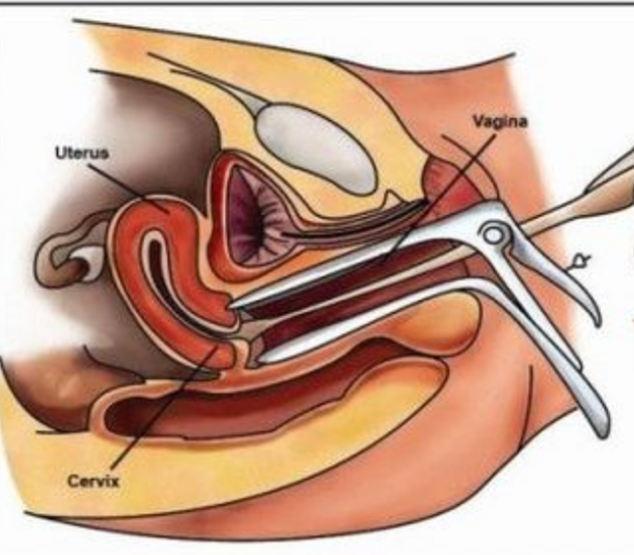

治療中人工陰道

治療中人工陰道漫畫

治療中人工陰道的

正在治療的人工陰道

治療中的人工陰道的

治療中的人工陰道

A:原發性陰道鱗狀上皮癌對放療比較敏感,可採用腔內鐳療、體外照射或放射性同位素局部應用等治療。一般早期陰道癌以腔內照射為主,放射源主要為鐳及鈷,現在多用銫,利用陰道容器,裝配不同劑量及放置不同時間。體外照射治療時放射量由主治醫師根據患者情況具體……

A:陰道癌就是指陰道內出現有惡性腫瘤。常見的陰道癌包括陰道腺癌、陰道基底細胞癌,以及陰道肉瘤或者疣狀癌等。而陰道癌常常是在陰道的側壁出現菜花樣贅生物,伴有血性的滲出分泌物流出,而且常常會有明顯的疼痛表現。主要的檢查手段就是需要做陰道鏡下的陰道壁……